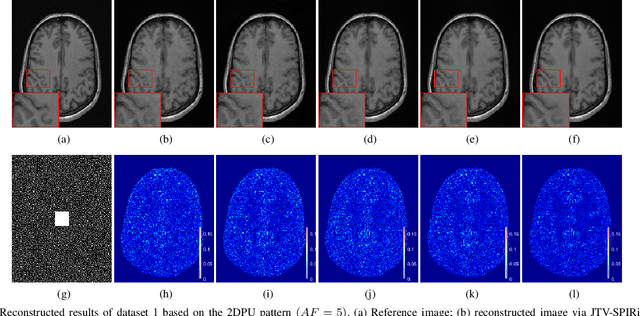

Abstract:Iterative self-consistent parallel imaging reconstruction (SPIRiT) is an effective self-calibrated reconstruction model for parallel magnetic resonance imaging (PMRI). The joint L1 norm of wavelet coefficients and joint total variation (TV) regularization terms are incorporated into the SPIRiT model to improve the reconstruction performance. The simultaneous two-directional low-rankness (STDLR) in k-space data is incorporated into SPIRiT to realize improved reconstruction. Recent methods have exploited the nonlocal self-similarity (NSS) of images by imposing nonlocal low-rankness of similar patches to achieve a superior performance. To fully utilize both the NSS in Magnetic resonance (MR) images and calibration consistency in the k-space domain, we propose a nonlocal low-rank (NLR)-SPIRiT model by incorporating NLR regularization into the SPIRiT model. We apply the weighted nuclear norm (WNN) as a surrogate of the rank and employ the Nash equilibrium (NE) formulation and alternating direction method of multipliers (ADMM) to efficiently solve the NLR-SPIRiT model. The experimental results demonstrate the superior performance of NLR-SPIRiT over the state-of-the-art methods via three objective metrics and visual comparison.